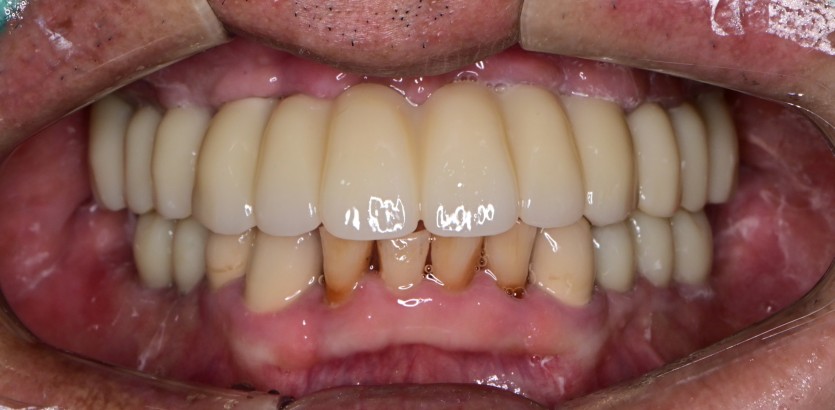

만 68세 상악 전체 임플란트 증례(하악 일부)

상악 전체 임플란트 증례입니다.(하악 일부)

15개의 임플란트로 완성하였습니다.